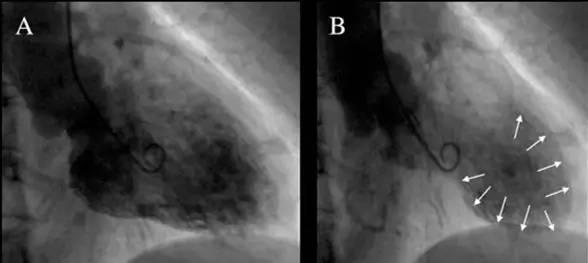

2012年,重庆31岁的贾女士失恋后,不吃不喝地在床上躺了2天,强烈的心口疼痛让她几乎不能呼吸,后被家人送进医院,经过心脏超声检查显示心肌出现扩张,但冠脉造影却发现一切正常,医生诊断她患上了“应急性心肌病”,俗称“心碎综合征”。

有条件的还需在医院积极进行冠状动脉造影,以指导鉴别诊断和治疗。